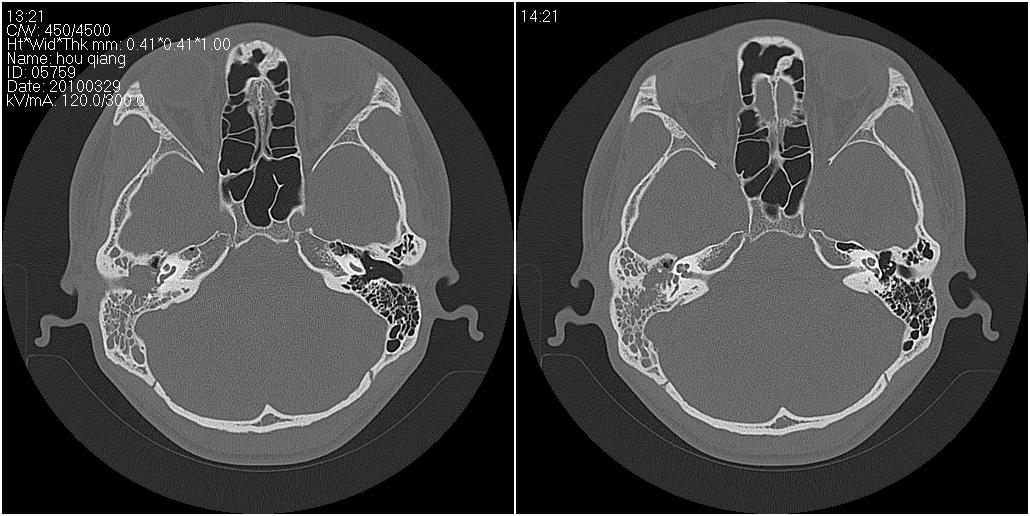

标题: CT25419:男性,18岁。右耳肿、痛5个多月。 [打印本页]

标题: CT25419:男性,18岁。右耳肿、痛5个多月。

右侧中耳乳突炎累及外耳道,鼻咽腺样体肥大。

1)右侧慢性中耳乳突炎并右侧中耳腔及外耳道肉芽肿或胆脂瘤形成。2)鼻咽腺样体肥大。